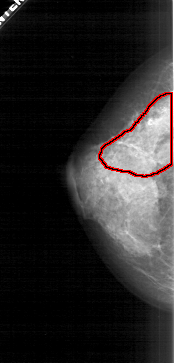

A_1932_1.LEFT_MLO

FILE: A_1932_1.LEFT_MLO.OVERLAY

TOTAL_ABNORMALITIES 1

ABNORMALITY 1

LESION_TYPE CALCIFICATION TYPE PLEOMORPHIC DISTRIBUTION SEGMENTAL

ASSESSMENT 5

SUBTLETY 4

PATHOLOGY MALIGNANT

TOTAL_OUTLINES 1

BOUNDARY